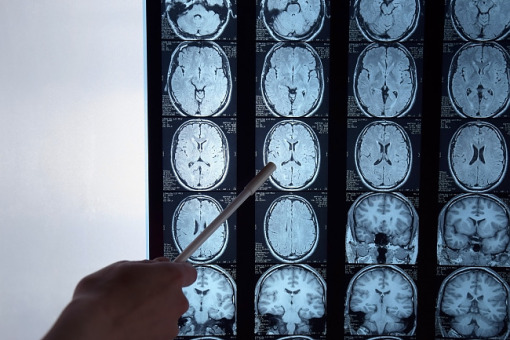

Amerykańska Agencja ds. Żywności i Leków (FDA) zatwierdziła tenekteplazę do leczenia ostrego udaru niedokrwiennego mózgu u dorosłych.

Udar mózgu jest piątą najczęstszą przyczyną zgonów i główną przyczyną długotrwałej niepełnosprawności w USA.